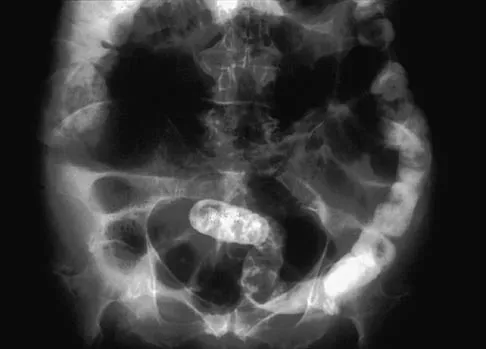

A 65-year-old woman has nausea, vomiting, and abdominal distention after undergoing total knee arthroplasty 48 hours ago. An abdominal radiograph is shown in Figure 14. Associated risk factors for this disorder include

Explanation